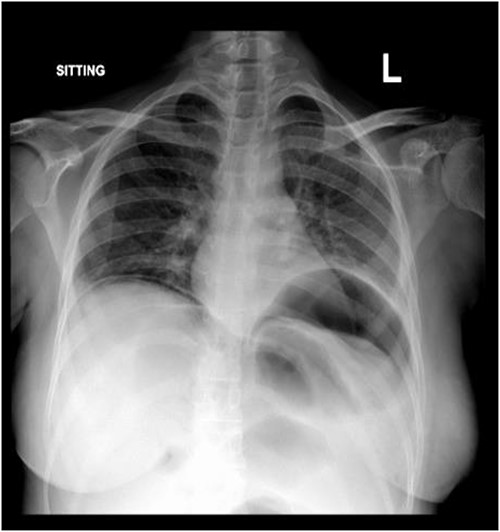

Subdiaphragmatic free air was detected on the posteroanterior chest radiograph, without air insufflation by nasogastric tube (Fig. 1).